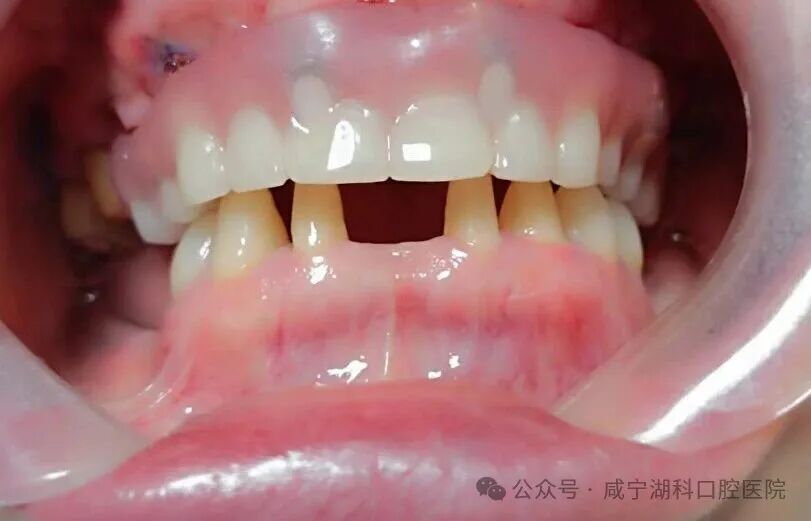

经过多方比较,1月25日,胡阿姨最终选择了刘伟院长为她进行穿翼种植,最终当天拔掉上颌两颗松动牙,保留了2颗大磨牙,植入5颗种植体,当天拔牙当天种当天戴固定牙。她说:“毕竟湖科口腔口碑很好,种植牙是很考验医生技术的手术,既然要做,就要找靠谱的、术后维护有保障的医院,技术过硬的医生。”

更让胡阿姨感到暖心的是,术后护理团队持续跟进,多次电话回访并耐心叮嘱注意事项,全面保障康复进程顺畅。过几天胡阿姨下颌的四颗种植牙也将在湖科口腔完成。

穿翼种植术可以实现当天种牙、当天修复,缩短治疗周期。